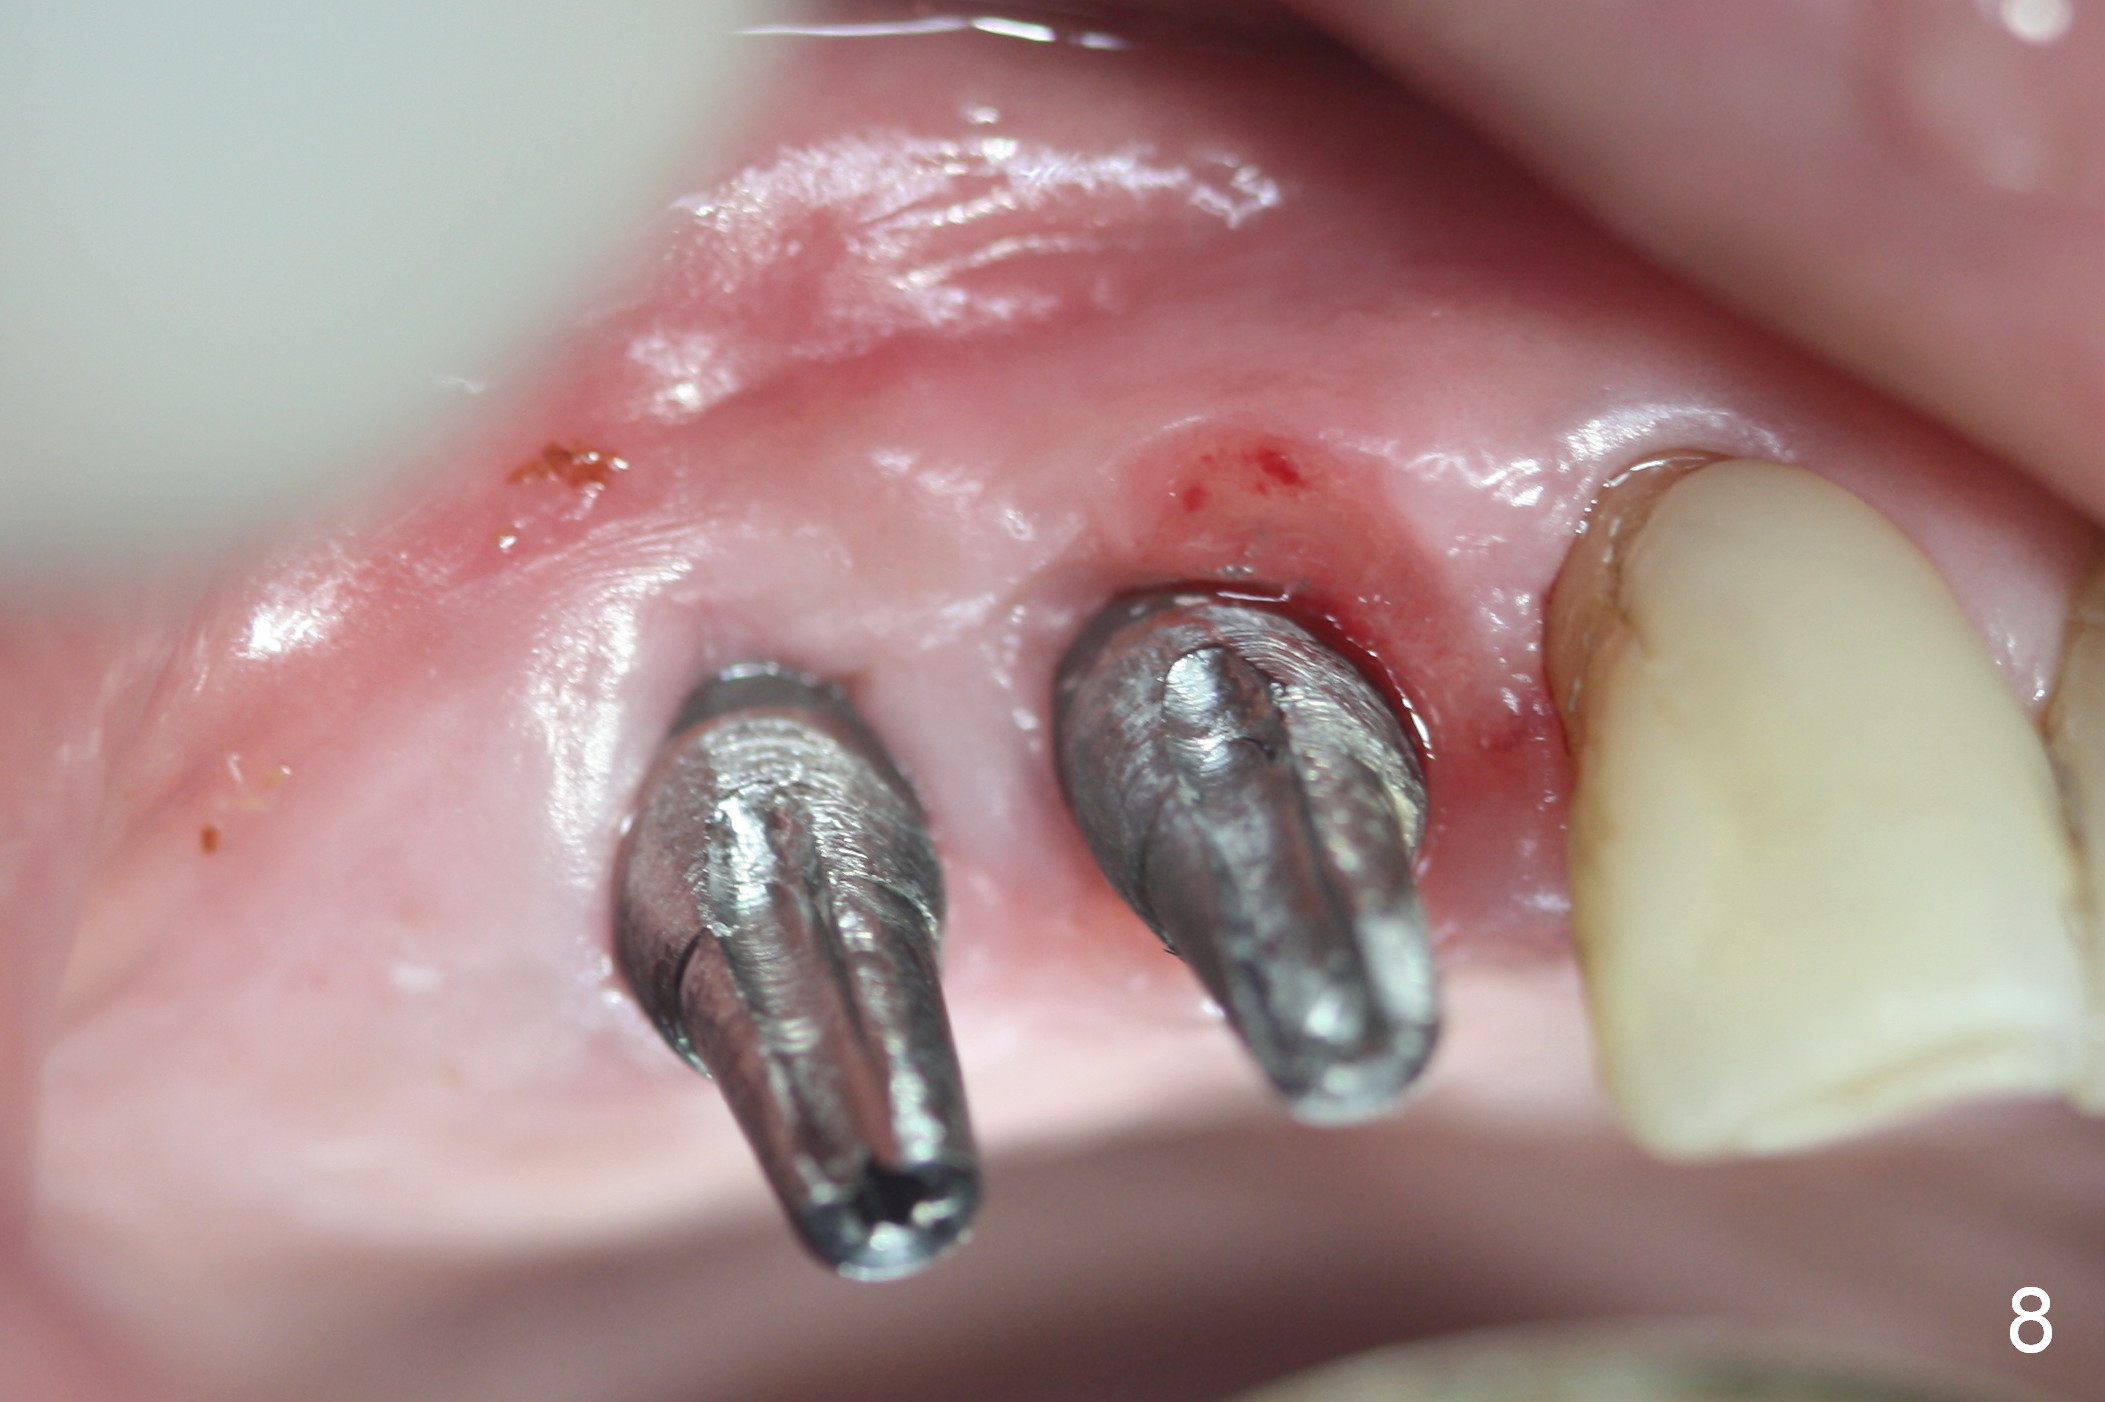

Bone density in the distal gap of #5 appears to have increased 3 months postop (Fig.7).  Prior to definitive restoration cementation (3.5 months postop), the buccal plate does not collapse (Fig.8).  There is no occlusal contact of the new restorations (Fig.9 *), probably due to bite discrepancy (Fig.10,11).